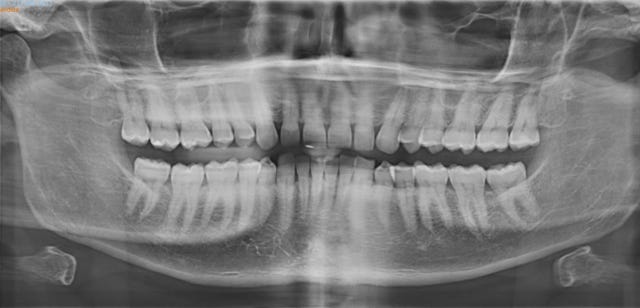

Mi dentista me ha dicho que llevo un tiempo apretando muy fuerte los dientes. No dormido, como hace alguna gente, sino durante el día, frente a la vida. Aparentemente, esa es la causa de las dos fisuras que se han abierto en mis molares, una en cada lado, perfectamente simétricas: